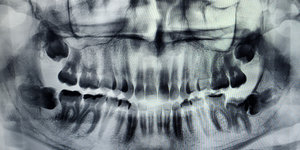

Обращаюсь к вам со следующей проблемой, от этой проблемы у меня уже кругом идет голова. Вообщем, заболел у меня зубик где-то года 2 назад, сделали рентген, обнаружили кариес, а так же на снимке увидели, что с левой стороны на нижней челюсти у меня выросла восьмерка, но она лежит под десной и упирается в соседний зуб, женщина в рентген кабинете посоветовала этот зуб удалить, я обращалась ко многим стоматологам и хирургу, вообщем все они сошлись во мнении, что если не беспокоит, то удалять не нужно, сказали что пусть он там под десной спокойно сидит себе и сидит до старости. Да и наслышана я об этом удалении страшные вещи, что и челюсть могут сломать при удалении и еще много неприятных вещей. Вообщем удалять я его не стала, и жила себе спокойно эти 2 года. Но сейчас он стал немного меня беспокоить, причем не только физически, я уже начинаю морально себе внушать что он болит. Мне постоянно кажется что у меня уже щека опухла и все в этом роде, хотя окружающие ничего не замечают. Но иногда он действительно меня беспокоит, периодически бывают пульсирующие боли и дискомфорт, не каждый день, но бывает. Подскажите пожалуйста, стоит ли удалять этот зуб? Мне очень страшно... НЕльзя ли его выпрямить как-нибудь? Обязательно удалять? К тому же выснилось что у меня с обоих сторон такие зубы

Рекомендации докторов, которые давали вам неправильные советы, совершенно не имеют медицинских объяснений. Зуб, который лежит горизонтально или под углом, наносит неповторимый вред семерке, и, в любом случае, вы его удалите, рано или поздно. Но зачем дожидаться обострений, отеков и повреждения соседнего зуба? Не понимаю, если я вам давал рекомендации удалить данный зуб, значит необходимо удалить.

• Необходимо сделать рентгеновский снимок, который называется ортопантомограмма, и обратиться к стоматологу-хирургу. По снимку можно определить расположение зуба и перспективу прорезывания. В случае если для полноценного прорезывания восьмого зуба места в зубном ряду недостаточно, то зуб подлежит удалению.